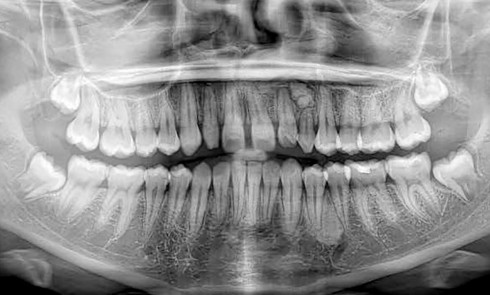

Après examen clinique, des photographies, des moulages, un panoramique et une téléradiographie de profil sont réalisés (fig. 1). Le traitement n’est pas simple mais le patient est motivé.

Après un an de traitement, une réévaluation est faite. De nouveaux clichés sont réalisés sur un nouvel appareil radiographique fraîchement installé (fig. 2). Les clichés obtenus sont de meilleure qualité et plus contrastés.

À l’examen de ces nouveaux clichés, une image radiologique de type « masse ronde » en regard des orbites se détache nettement. Immédiatement remontent mes souvenirs de cours de radio de l’examen du CECSMO. On nous apprenait à regarder la selle turcique et à reconnaître une tumeur. Une intime conviction s’impose : mon patient a une tumeur…

Je retourne immédiatement vers les premiers clichés avant traitement : l’image radiologique de la masse était déjà là !

Le volume semble identique, ce qui me rassure néanmoins sur le caractère peu évolutif. Je consulte sa fiche médicale, mais aucun problème de santé n’est mentionné.